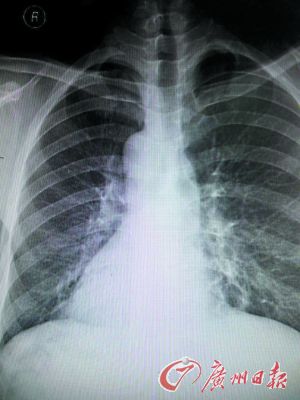

X光片上袁先生的心臟陰影在右邊。

X光片上患者的心臟陰影在右邊。

東莞現鏡面人,五臟六腑長的位置和一般人相反,正常人的心臟、脾臟在左側,肝臟在右側。但日前,東莞市第八人民醫院收治的一名病人正好相反,他的心臟、脾臟在右邊,肝臟在左邊。

醫生趕快拿起聽診器聽診心音區,發現患者右側心音較左側明顯,跟常人相反。經胸片、心電圖及B超等檢查后,確診患者為急性化膿性闌尾炎內臟反位,也就是“鏡面人”得了闌尾炎。